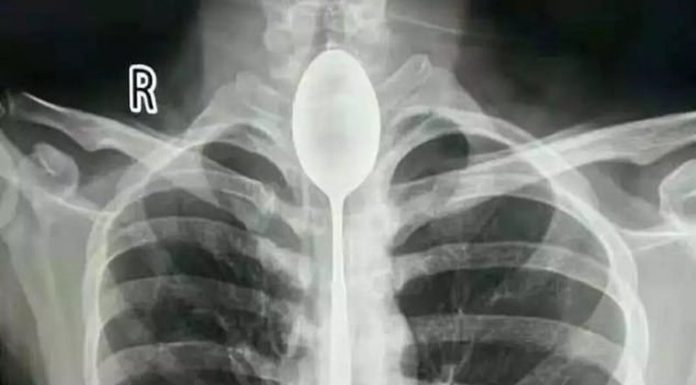

Durante um jantar de amigos, um indivíduo chinês engoliu uma colher de 20 centímetros depois de perder uma aposta. Como conseguia respirar e comer normalmente, achou desnecessário consultar um médico. Resultado da aposta: ficou com a colher no esófago durante um ano.

Um homem chinês perdeu uma aposta durante um jantar de amigos. Entre muita comida e bebida, a consequência...